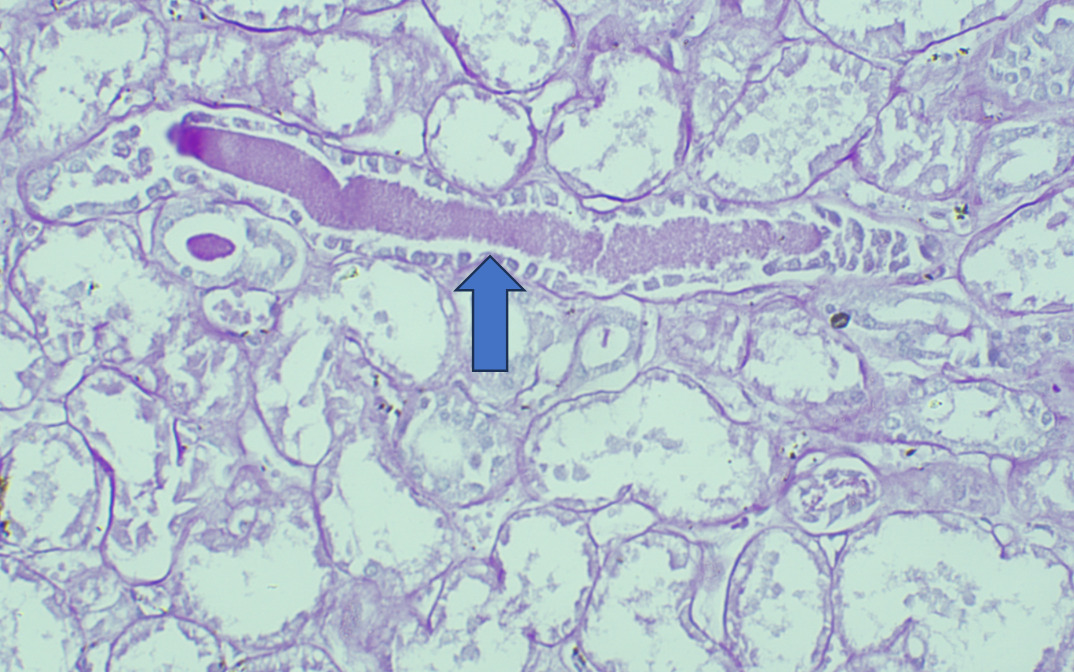

On Light microscopy, The H &E-stained sections of renal biopsy showed features of acute tubular epithelial cell injury with swollen, attenuated lining epithelium. Numerous tubules showed pink to red brown casts in the lumen which were grainy to globular and ropy at places. (Figure 1). The casts appeared weakly PAS positive (Figure 2) and fuchsinophilic on MT stain (Figure 3). On IHC, these casts gave positive staining for myoglobin (Figure 4).

On Light microscopy, Renal biopsy shows features of acute tubular injury (ATI) with attenuation of tubular epithelial cells, cytoplasmic vacuoles, brush border loss and sloughed out intratubular epithelial cells.3,4,13

According to one study, other associated finding may be of arterial sclerosis and deposition of calcium oxalate.3 Myoglobin casts are usually appeared eosinophilic to brown granular in H&E stain, are weakly PAS positive and fuchsinophilic in MT stain. Differential diagnosis of Myoglobin casts includes other pigment casts like haemoglobin casts and bile casts.5,11–13